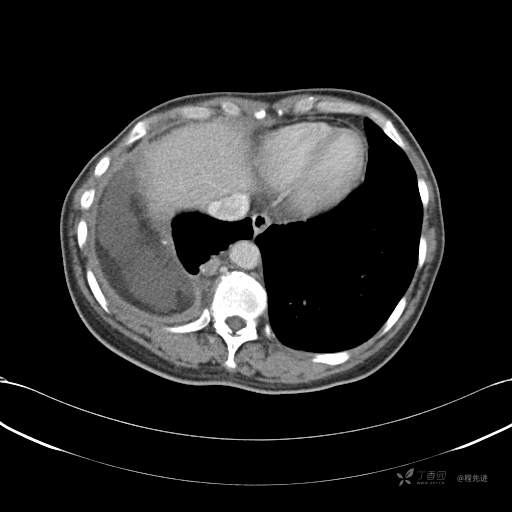

患者性别:女

患者年龄:51岁

简要病史:胸闷半年